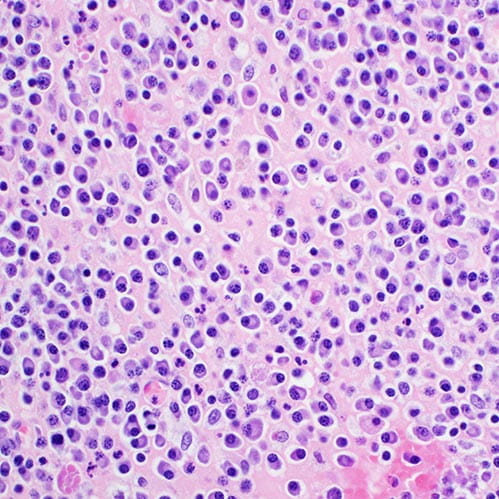

H&E stain, light microscopy, multiple myeloma

Multiple Myeloma

plasma cells

Targeting Plasma Cells for Organ Transplantation